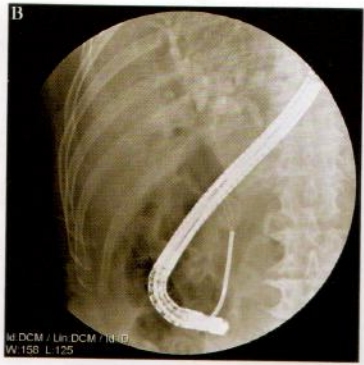

通过经内镜乳头切开(EST)技术可以使80%的胆管结石顺利取出,小于1cm的结石,一般均可通过网篮、球囊完整取出。但对于较大结石,特别是大于2cm的结石直接用网篮或球囊取出会比较困难,强行取出可能造成乳头撕裂、穿孔或结石嵌顿因此,对于大于2cm的结石,应在EST后进行碎石,再用网篮或球囊取石(图10-6-1)。

图10-6-1 | A、B.  胆管内碎石器碎石;C. 碎石后取出乳头